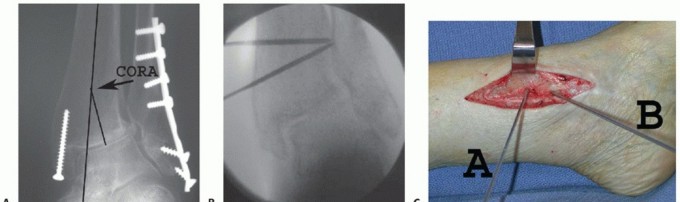

Determining the CORA of the deformity (see FIG 1): The CORA is the intersection of the two lines that define the deformity, lines that are drawn to represent the mechanical axes of the proximal (line A) and distal segments (line B).

FIG 1 • Preoperative AP radiograph of a patient with severe valgus malalignment of the distal tibia, due to physeal disturbance from adjacent osteochondroma that was excised in a previous procedure. Note the location of center of rotation of angulation (CORA) at the intersection of two lines that represent the mechanical axes of the proximal (line A) and distal segments (line B). Line A, also representing the tibial mechanical axis (which in the case of the tibia coincides with the anatomic axis), and another line that is drawn to represent the distal tibial articular surface form the tibial ankle surface (TAS) angle on the AP view with a magnitude of 108 degrees.

When correcting tibial deformity, perform the osteotomy at the CORA (TECH FIG 1).

In select cases, the supramalleolar osteotomy is not performed at the CORA. In some distal tibial deformities, the CORA may be located at the ankle joint, where the osteotomy is not feasible,

and the translational component must be compensated. Also, in ankle deformity with only minor alterations of the TAS angle and when detrimental translation of the distal fragment is not a major concern, we generally perform the osteotomy 4 to 5 cm proximal to the medial malleolar tip.

TECH FIG 1 • Medial closing wedge supramalleolar osteotomy. A. Using a preoperative radiograph, the center of rotation of angulation (CORA) is located at the intersection of two lines that represent the mechanical axes of the proximal and distal segments. B. Under fluoroscopy, a Kirschner wire is inserted to the tibia perpendicular to the mechanical axis and a second Kirschner wire is inserted parallel to the ankle joint line intersecting the first wire, ideally at the apex of the deformity. C,D. Guide pin wires used to perform a closing medial wedge osteotomy. Pin A has been inserted to the tibia perpendicular to the mechanical axis and pin B has been inserted parallel to the ankle joint line, intersecting pin A at the apex of the deformity. E. The cut wedge. The pins have been used as a guide for the tibial cuts, whereas the size of the wedge has been determined during the preoperative planning. (continued)